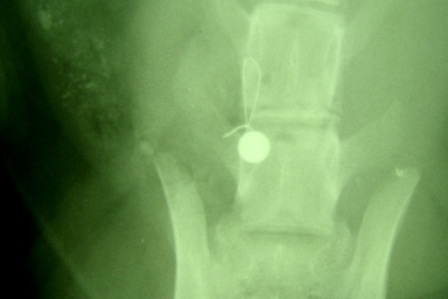

Manchmal gibt es Dinge, die man kaum fassen kann. Nach einem Autounfall wurde mir

eine kleine Katze mit einem Bruch eines Lendenwirbels vorgestellt. Trotz der massiven Verschiebung des Wirbels war sie nicht vollständig gelähmt. Auf besonderes Drängen des Besitzers konnte ich die Wirbelsäule wieder zurückdrehen und, zwar relativ einfach, aber effektiv mit einem Draht und einer Schraube fixieren. Tatsächlich ist es so die dass Katze eín fast normales Leben führen kann und auch schon wieder Bäume erklettert.

Keiner hätte das für möglich gehalten bei dem Röntgenbefund.